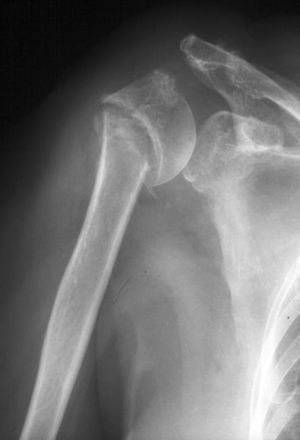

En el caso de que consideremos el tratamiento quirúrgico, se debe realizar un estudio preoperatorio completo de las características del paciente y de la fractura. Es recomendable un examen neurológico exhaustivo, comprobando la funcionalidad del deltoides. El estudio radiológico debería incluir al menos una proyección anteroposterior en el plano escapular y una proyección axilar verdadera (fig. 2). Se deben evaluar: el estado del fragmento cefálico, el déficit óseo en el foco de pseudoartrosis, la presencia o no de necrosis de la cabeza humeral y la integridad del cartílago articular. El uso de la tomografía computerizada (TC) podría ser especialmente útil en la evaluación de las fracturas con división de la cabeza y para cuantificar el desplazamiento de las tuberosidades.

A) Radiografía anteroposterior en plano escapular de hombro izquierdo en el que se sospecha ausencia de consolidación tras fractura de húmero proximal en 3 partes. B) Radiografía axilar verdadera de hombro izquierdo en la que se aprecia la pseudoartrosis a nivel del cuello quirúrgico y la consolidación parcial del troquíter.